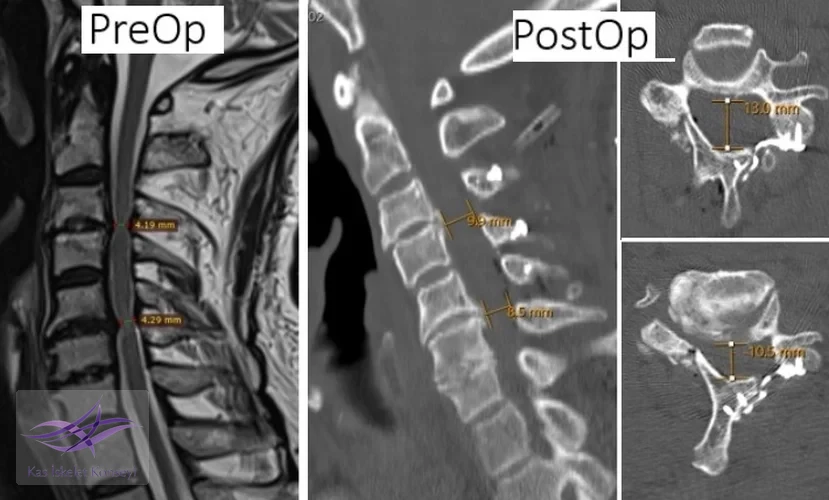

İncelemeler: Servikal MRG'de dar kanal saptandı, kanal ön-arka çapı 5 mm'nin altına inmişti.

Klinik Seyir: Hastaya cerrahi dekompresyon kararı verildi. C3-C6 seviyelerinde servikal laminoplasti yapıldı. Postop BT incelemelerinde kanal çapının arttığı görüldü. Hastada cerrahiye ait bir komplikasyon olmadı ve klinik durum belirgin düzeldi.

Resim 2. Preop ve postop incelemelerde kanal çapındaki artış görülmekte.